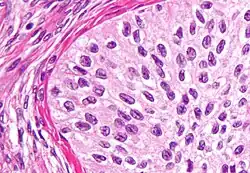

High magnification micrograph of a Brenner tumor, a type of surface epithelial-stromal tumor. H&E stain. | |

Brenner tumor

Brenner tumors are uncommon surface-epithelial stromal cell tumors in which the epithelial cell (which defines these tumors) is a transitional cell. These are similar in appearance to bladder epithelia. The tumors may be very small to very large, and may be solid or cystic. Histologically, the tumor consists of nests of the aforementioned transitional cells within surrounding tissue that resembles normal ovary. Brenner tumors may be benign or malignant, depending on whether the tumor cells invade the surrounding tissue.